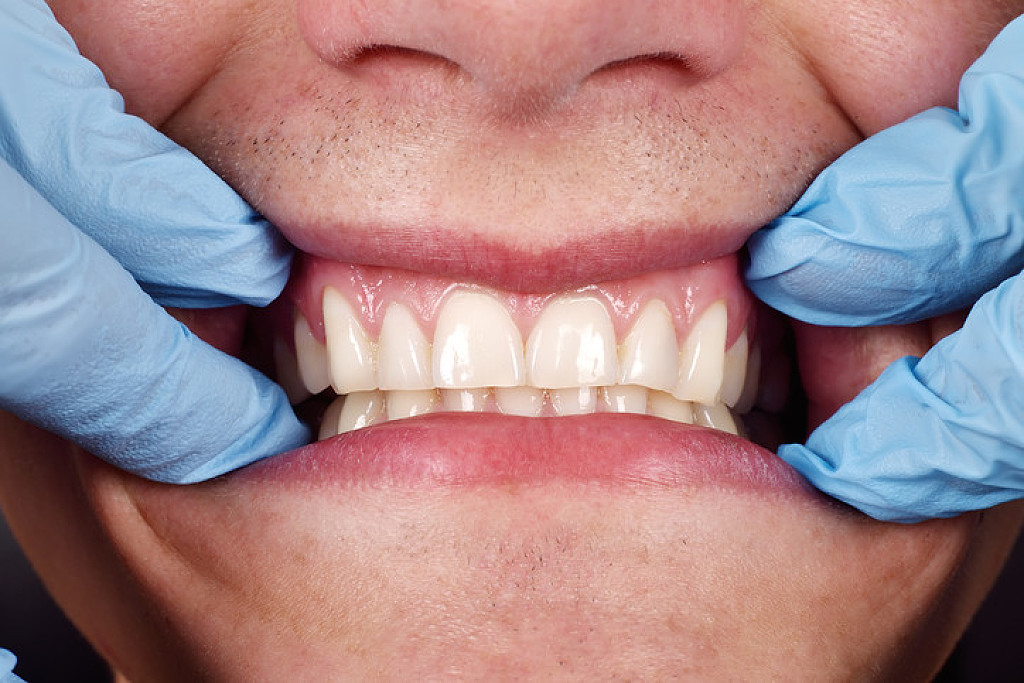

Surgical Removal:

In the end, the overgrown gums may need to be surgically removed. The AAOM notes that good oral hygiene, especially the effective removal of plaque between the teeth, can alleviate the condition. In the case of drug-induced overgrowths, if patients are not able to discontinue the medication, surgical removal may be the only effective treatment. This can be done with a scalpel or laser.

However, if the root cause is not adjusted, the enlargement will return, and surgery may have to be performed numerous times. Pressure devices that look like night guards are sometimes used to try and limit the rate of rebound of the tissues. Also, your dentist may have you return every three months to clean the areas to limit the effects of inflammation on the soft tissues.